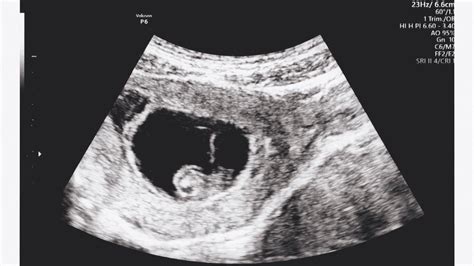

Az első ultrahangos vizsgálat során általában a nőgyógyász megerősíti a menstruációs ciklus alapján kiszámított teherbeesés időpontját, és amennyiben a kettő között jelentős eltéréseket tapasztal, további vizsgálatokra lehet szükség.

Az ultrahangos vizsgálat általában a megtermékenyülés utáni 23-25.-ik napon tudja először kimutatni a terhességet (ekkor a magzat nem látszik még, csak a petezsák megléte).

Az első ultrahangos szűrést általában a terhesség 12. A szülés során az anya méhében fejlődő magzat világra jön.

A terhesség megállapításának legpontosabb módja a nőgyógyászati vizsgálat, amely nemcsak a terhesség tényét, hanem az embrió korát, vagyis a fogantatás idejét is meg tudja határozni az ultrahangos vizsgálat segítségével.

A modern ultrahangos készülékek meglehetősen nagy segítséget nyújtanak ebben a tekintetben, de a legtöbb orvos a terhesség idejének megállapításában és a szülés várható idejének kiszámításában a nő utolsó menstruációs ciklusának első napját fogja figyelembe venni.